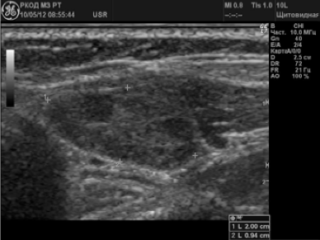

УЗИ лимфатических узлов шеи – один из методов диагностики патологий. Таким образом обнаруживают лимфомы, раковые опухоли, лимфадениты, лейкемию, микозы, разнообразные воспалительные процессы, связанные с заболеваниями уха, горла, носа. Методика простая, безболезненная и информативная.

Врач изучает полученное изображение, оценивая размеры, форму структуры, консистенцию, эхогенность, соотношение с окружающими тканями. По этим данным и производится диагностика.

- Форма – в норме лимфоузлы шеи и головы на УЗИ выглядят как округлые, овальные или бобовидные образования с четкими, ровными контурами, возможно с утолщениями.

- Структура – обычно это гипоэхогенные образования с некотором уплотнением в средней части и с гиперэхогенным ровным ободком. Кисты или другие включения отсутствуют.

- Лимфаденит – проявляется как снижение эхогенности и изменение структуры.

- Лимфома – специфические признаки у нее отсутствуют, поэтому для подтверждения диагноза понадобится биопсия. На снимке лимфоузел теряет четкость и приобретает неоднородную структуру.